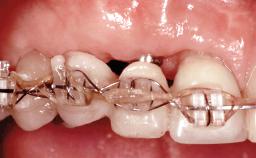

In November 2010, a 44-year-old woman presented to the Harvard School of Dental Medicine seeking options to replace her failing six-unit conventional prosthesis. Having served for approximately 10 years, the fixed partial denture had repeatedly needed recementation after chronic dislodgement over the past few months. Following these episodes, the patient requested further evaluation of her current prosthesis and showed interest in exploring other options for a fixed solution. The patient was in good overall health, presenting with no systemic contraindications to implant therapy or any history of allergies; she did not smoke and was on no medications. Being a well-motivated individual, she regularly saw her general dental practitioner and effectively complied with oral hygiene requirements.